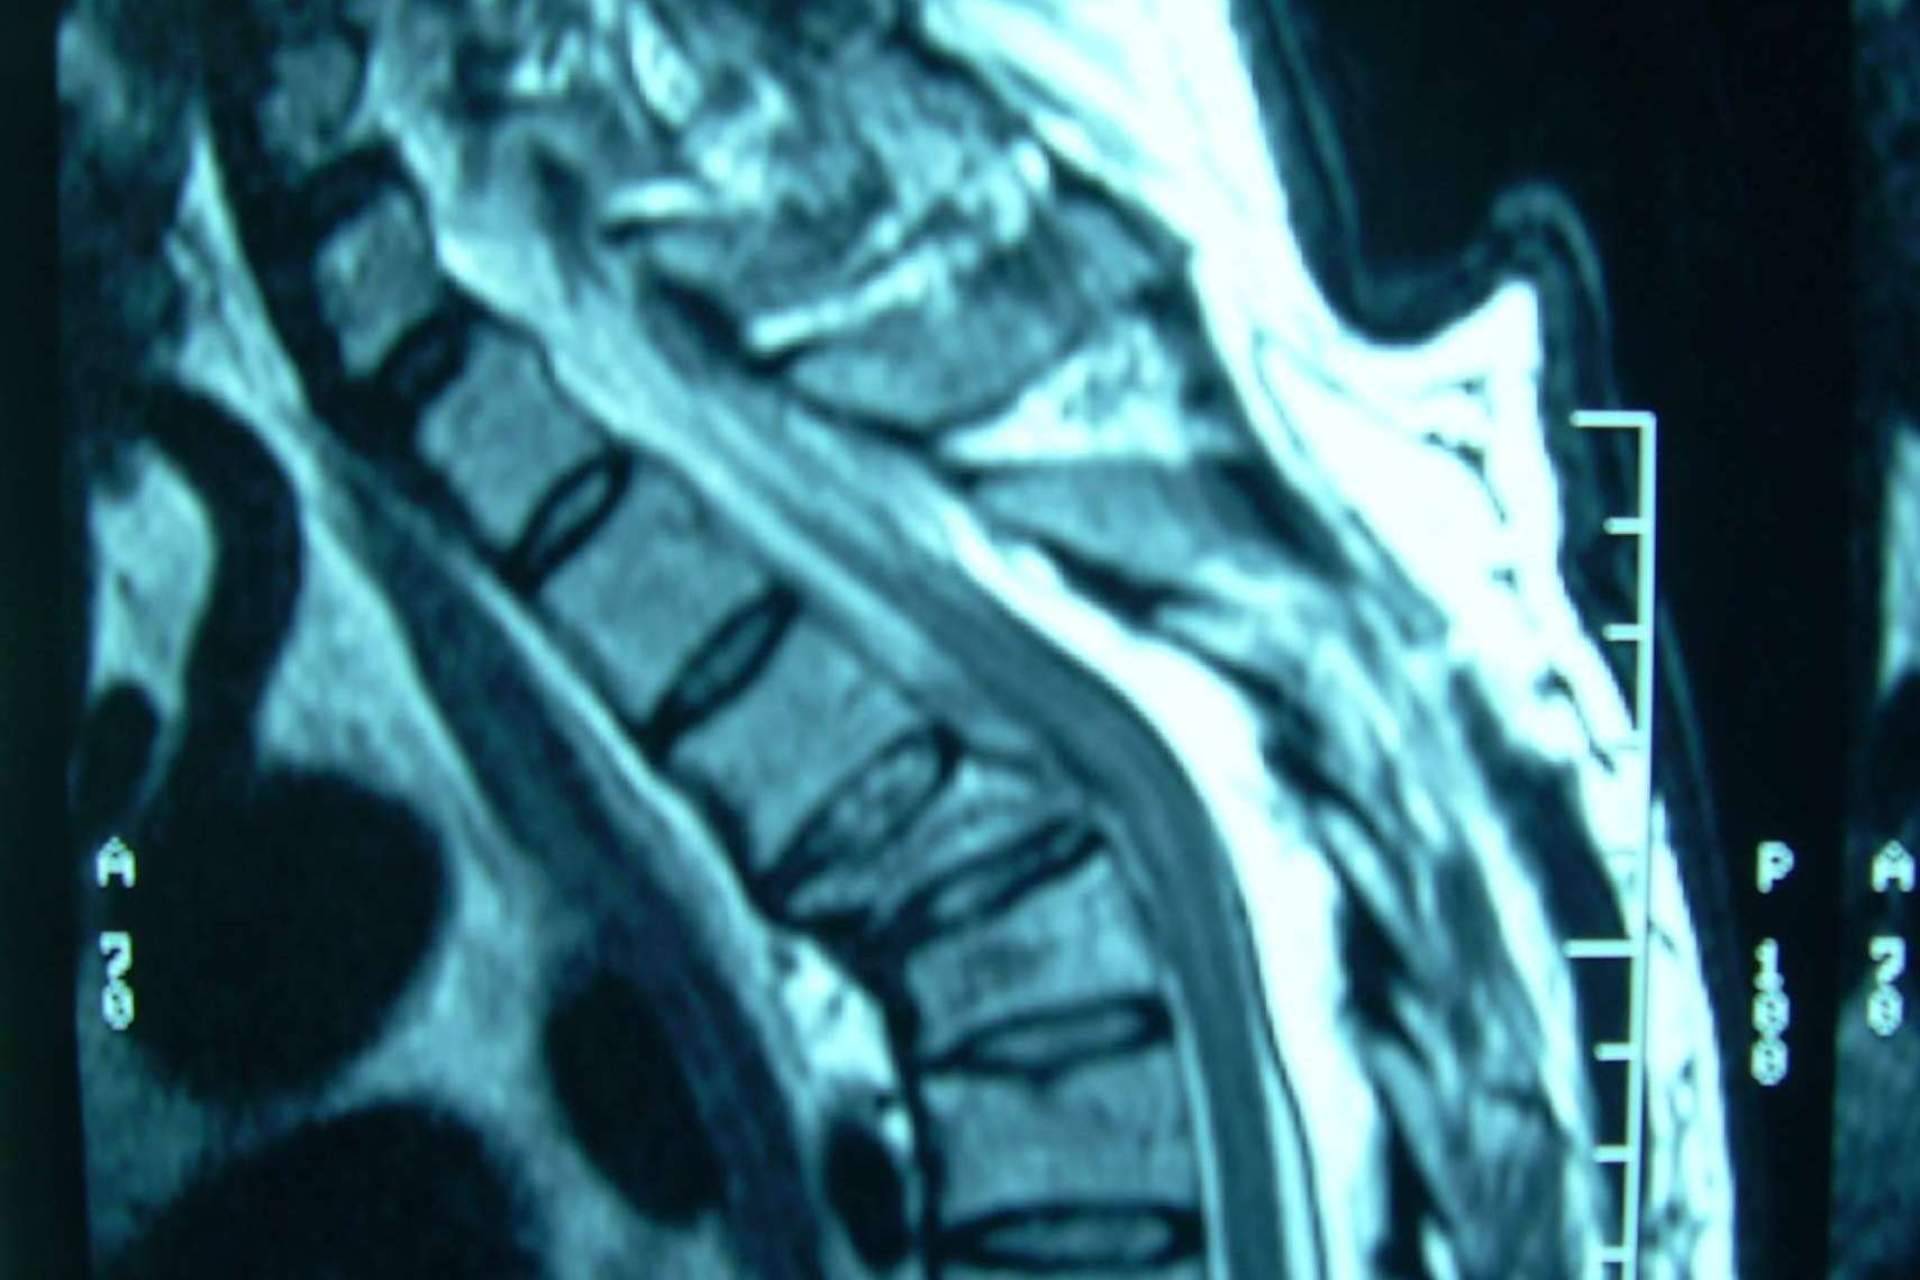

Las fracturas vertebrales son la ruptura en cualquier vértebra de la columna. Según la localización de la parte afectada, pueden traer secuelas en la zona cervical, torácica, lumbar, del sacro o del coxis.

Los dolores de fractura de la columna pueden deberse a la ruptura del hueso que puede manifestarse en el sitio de la lesión o a la distancia por algún nervio comprometido. También pueden ser por dolor neurológico que indica una mayor alerta porque compromete la parte sensitiva o motora, evidenciando que hubo un desplazamiento que está afectando la médula espinal. De cualquier forma, un especialista como los cirujanos de Neurocirugía Galarza deberá revisar al paciente y hacer un diagnóstico por medio de estudios específicos para definir cómo proceder.